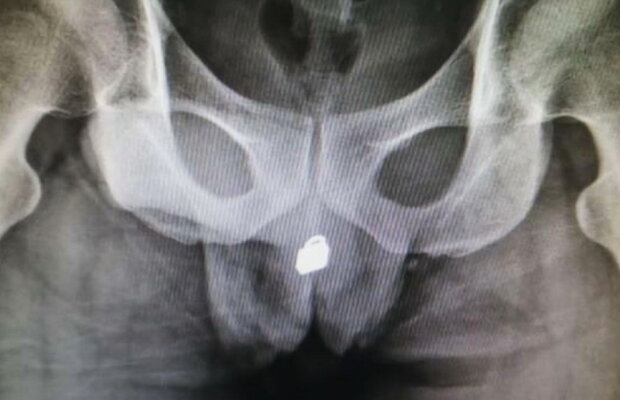

Şi-a băgat un lacăt în penis, iar ce a urmat pare desprins din filmele de comedie